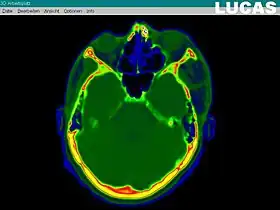

Image gathering ("segmentation") on the LUCAS workstation

Creating a virtual image of the patient

The most important component for CAS is the development of an accurate model of the patient. This can be conducted through a number of medical imaging technologies including CT, MRI, x-rays, ultrasound plus many more. For the generation of this model, the anatomical region to be operated has to be scanned and uploaded into the computer system. It is possible to employ a number of scanning methods, with the datasets combined through data fusion techniques. The final objective is the creation of a 3D dataset that reproduces the exact geometrical situation of the normal and pathological tissues and structures of that region. Of the available scanning methods, the CT is preferred,[1] because MRI data sets are known to have volumetric deformations that may lead to inaccuracies. An example data set can include the collection of data compiled with 180 CT slices, that are 1 mm apart, each having 512 by 512 pixels. The contrasts of the 3D dataset (with its tens of millions of pixels) provide the detail of soft vs hard tissue structures, and thus allow a computer to differentiate, and visually separate for a human, the different tissues and structures. The image data taken from a patient will often include intentional landmark features, in order to be able to later realign the virtual dataset against the actual patient during surgery. See patient registration.

Image analysis involves the manipulation of the patients 3D model to extract relevant information from the data. Using the differing contrast levels of the different tissues within the imagery, as examples, a model can be changed to show just hard structures such as bone, or view the flow of arteries and veins through the brain.